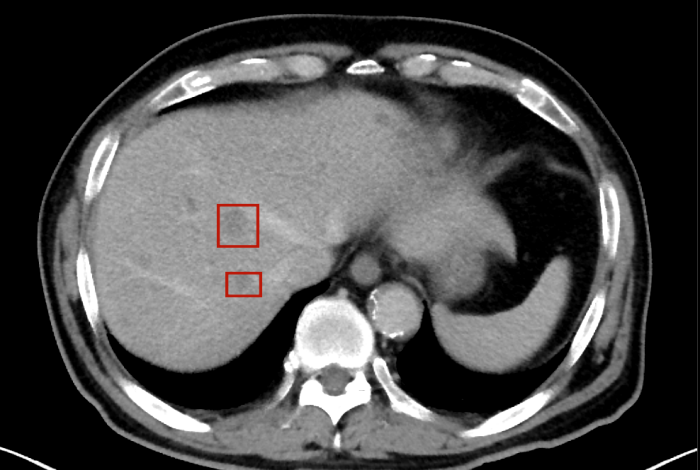

術(shù)后,萬秀萍為黃先生做進(jìn)一步的檢查,腹部磁共振(MRI)檢查顯示:肝臟區(qū)域出現(xiàn)了轉(zhuǎn)移病灶的陰影。

在腫瘤治療領(lǐng)域,一旦出現(xiàn)遠(yuǎn)處器官(如肝臟)轉(zhuǎn)移,通常意味著疾病進(jìn)入晚期階段。 肝膽外科專家會(huì)診后也給出了“目前無法通過手術(shù)達(dá)到根治”的結(jié)論。這個(gè)診斷,像一塊沉重的巨石,壓在了黃先生和家人的心頭。

轉(zhuǎn)移病灶的陰影

目前,黃先生的腫瘤活動(dòng)已得到有效抑制,肝臟轉(zhuǎn)移灶未見爆發(fā)性進(jìn)展,病情整體保持穩(wěn)定。